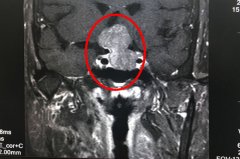

DSA血管栓塞术+脑瘤切除术 巨大脑膜瘤被成功摘除

很多医院不愿意收治,因为手术风险太大了。现在患者在蓝十字术后恢复良好,家属满意,我也放心了。历经5个小时,为王先生(化名)做完左侧额顶巨大占位切除术两天后,侯增欣主任(政府特殊津贴专家)这么对小...【详细】